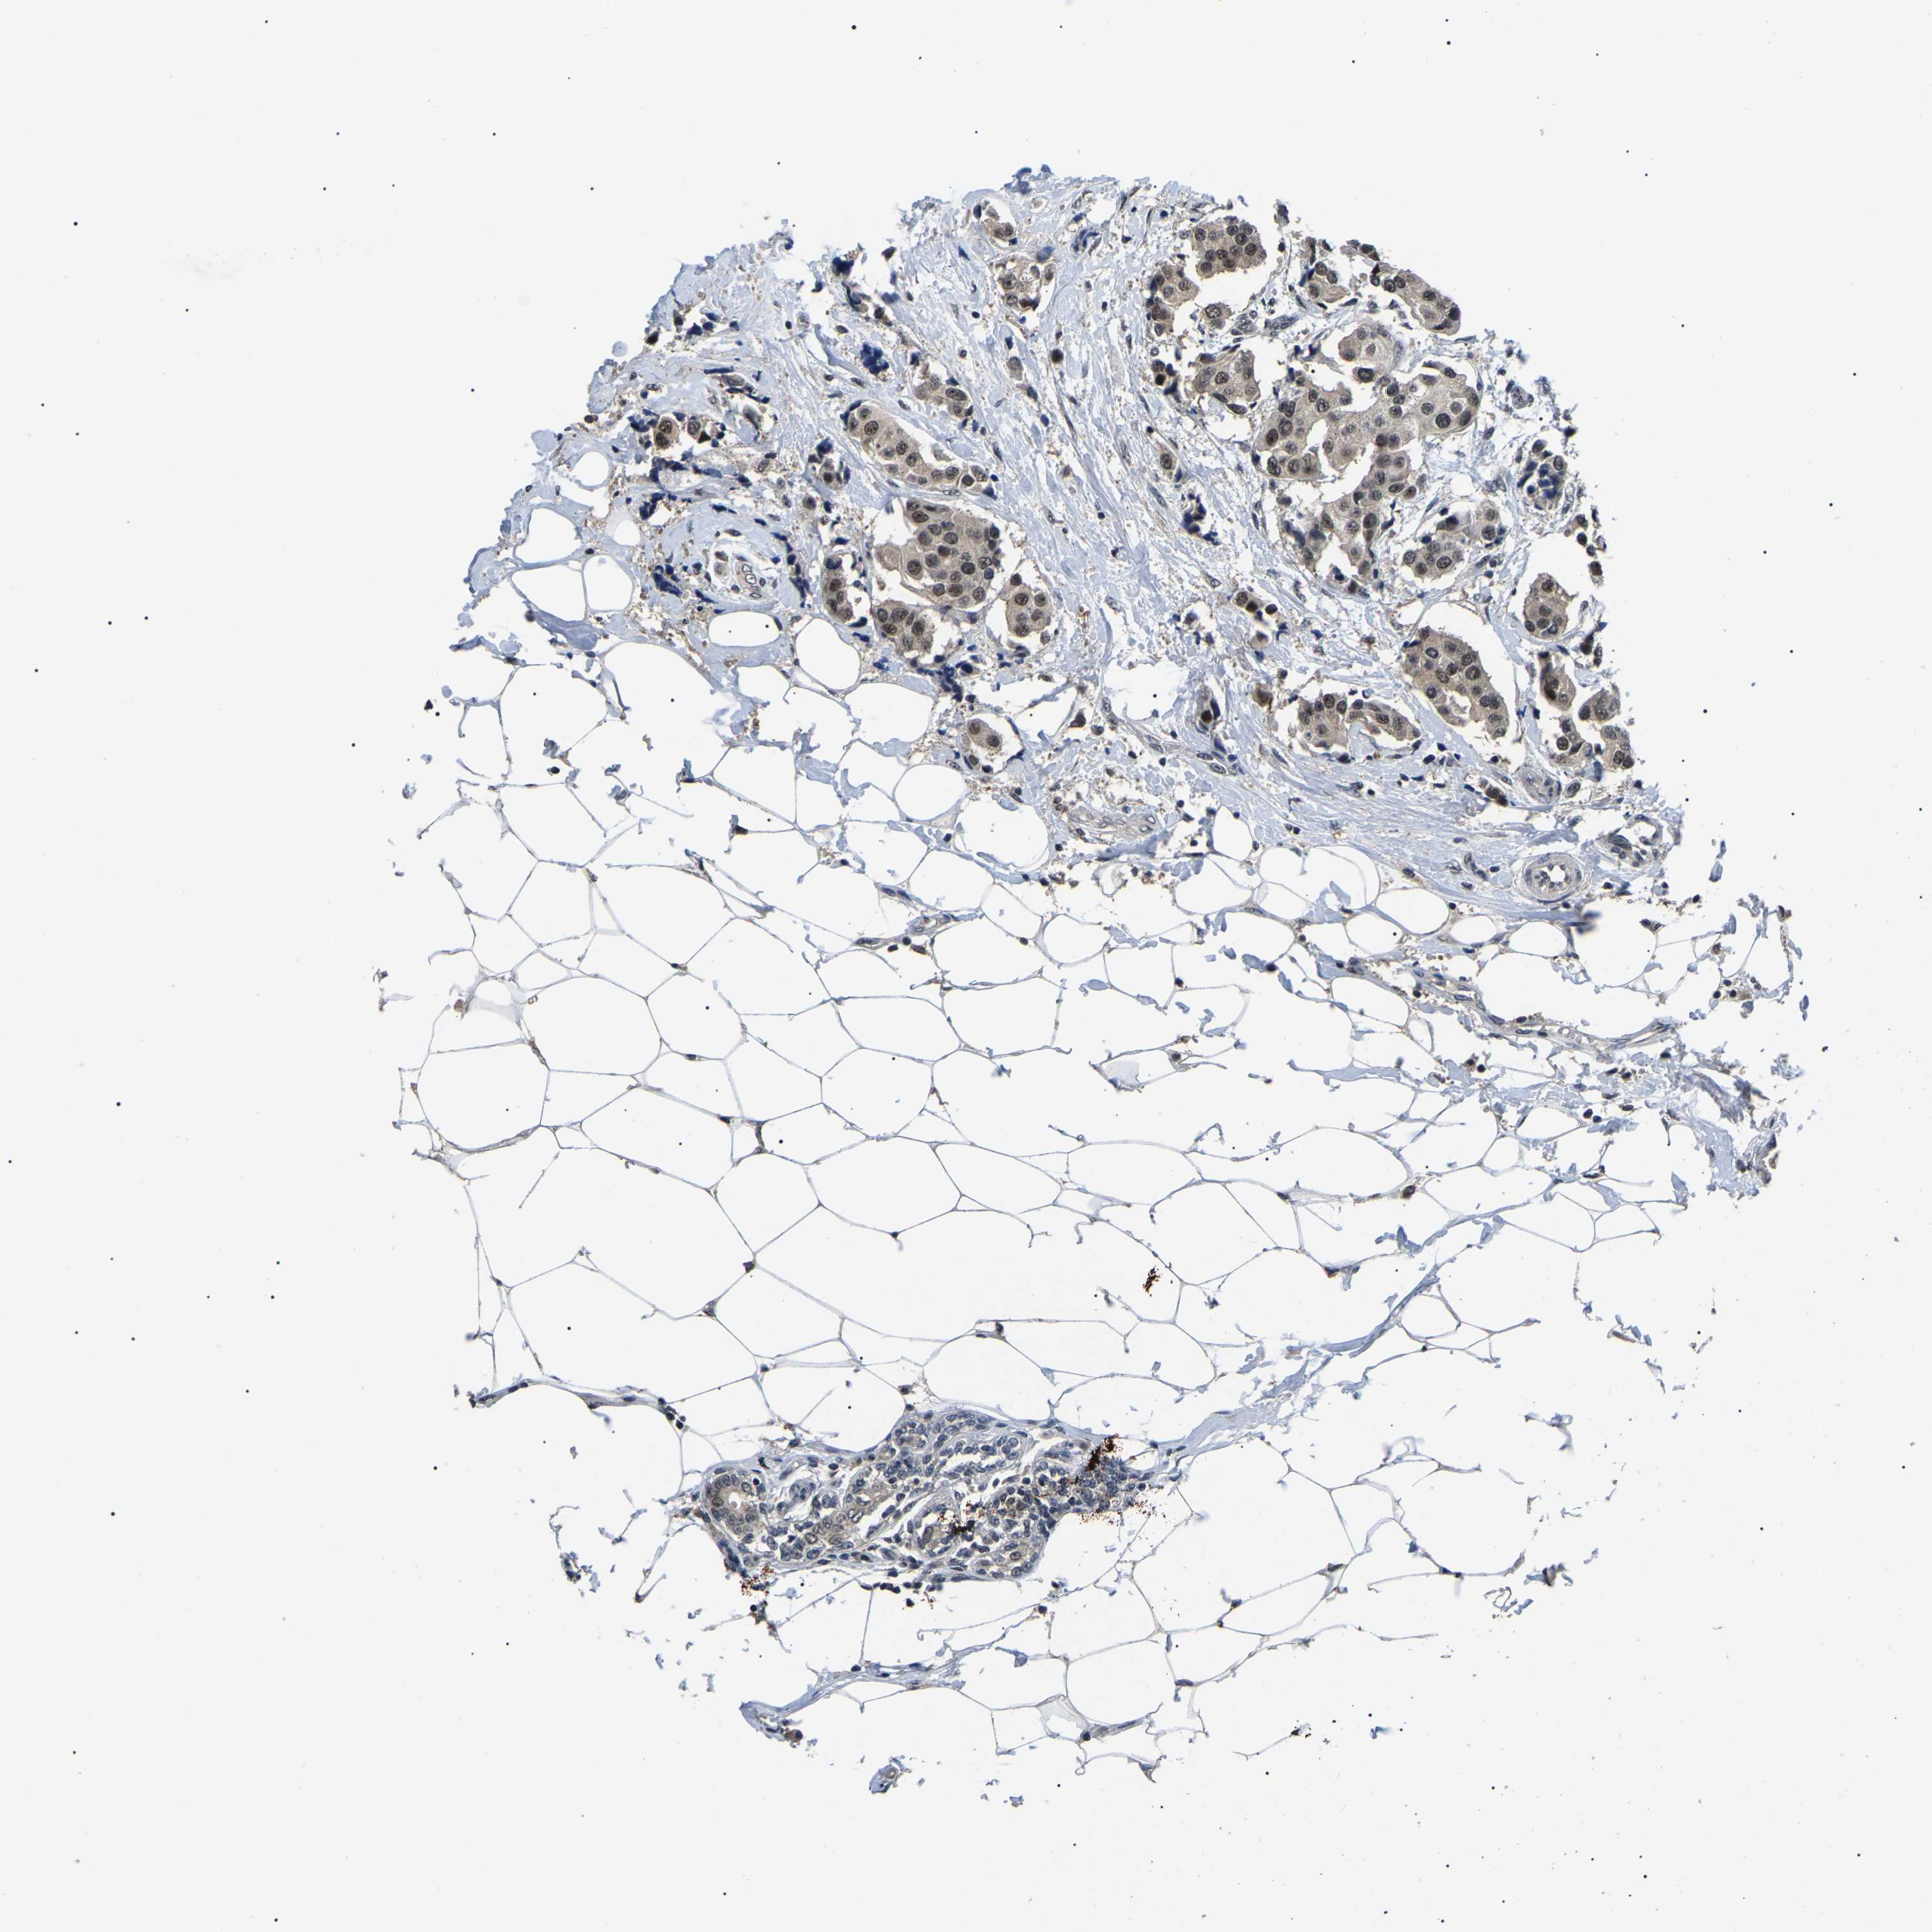

CANCER BREAST CANCER Show tissue menu

BRCA TCGA BRCA VALIDATION PROTEIN EXPRESSION